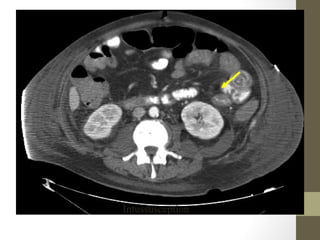

Radiology- CT Scan

• Detect leaking AAA (in stable patient)

• Evaluate for renal calculi, appendicitis, perforation (free air),

diverticulitis, abscess, mesenteric ischemia, masses, obstruction

• Sensitivity and specificity vary

• Not a place for unstable patients

• Contrast

• PO and IV contrast in most patients

• sometimes rectal contrast is helpful to look for large bowel problems

(appendicitis)

• In patients with renal insufficiency

• give IV contrast judiciously in patients

• consider ultrasound as an alternative if possible

• a creatinine > 1.5 usually requires bicarbonate and fluid hydration to

minimize contrast nephropathy

• 62.

Rapid Case #4 •65 yo male • Hx of HTN, Renal Colic x3 episodes • Low back pain- ?new pain • Abd: obese, soft, no masses palpated • U/S shows 7cm AAA